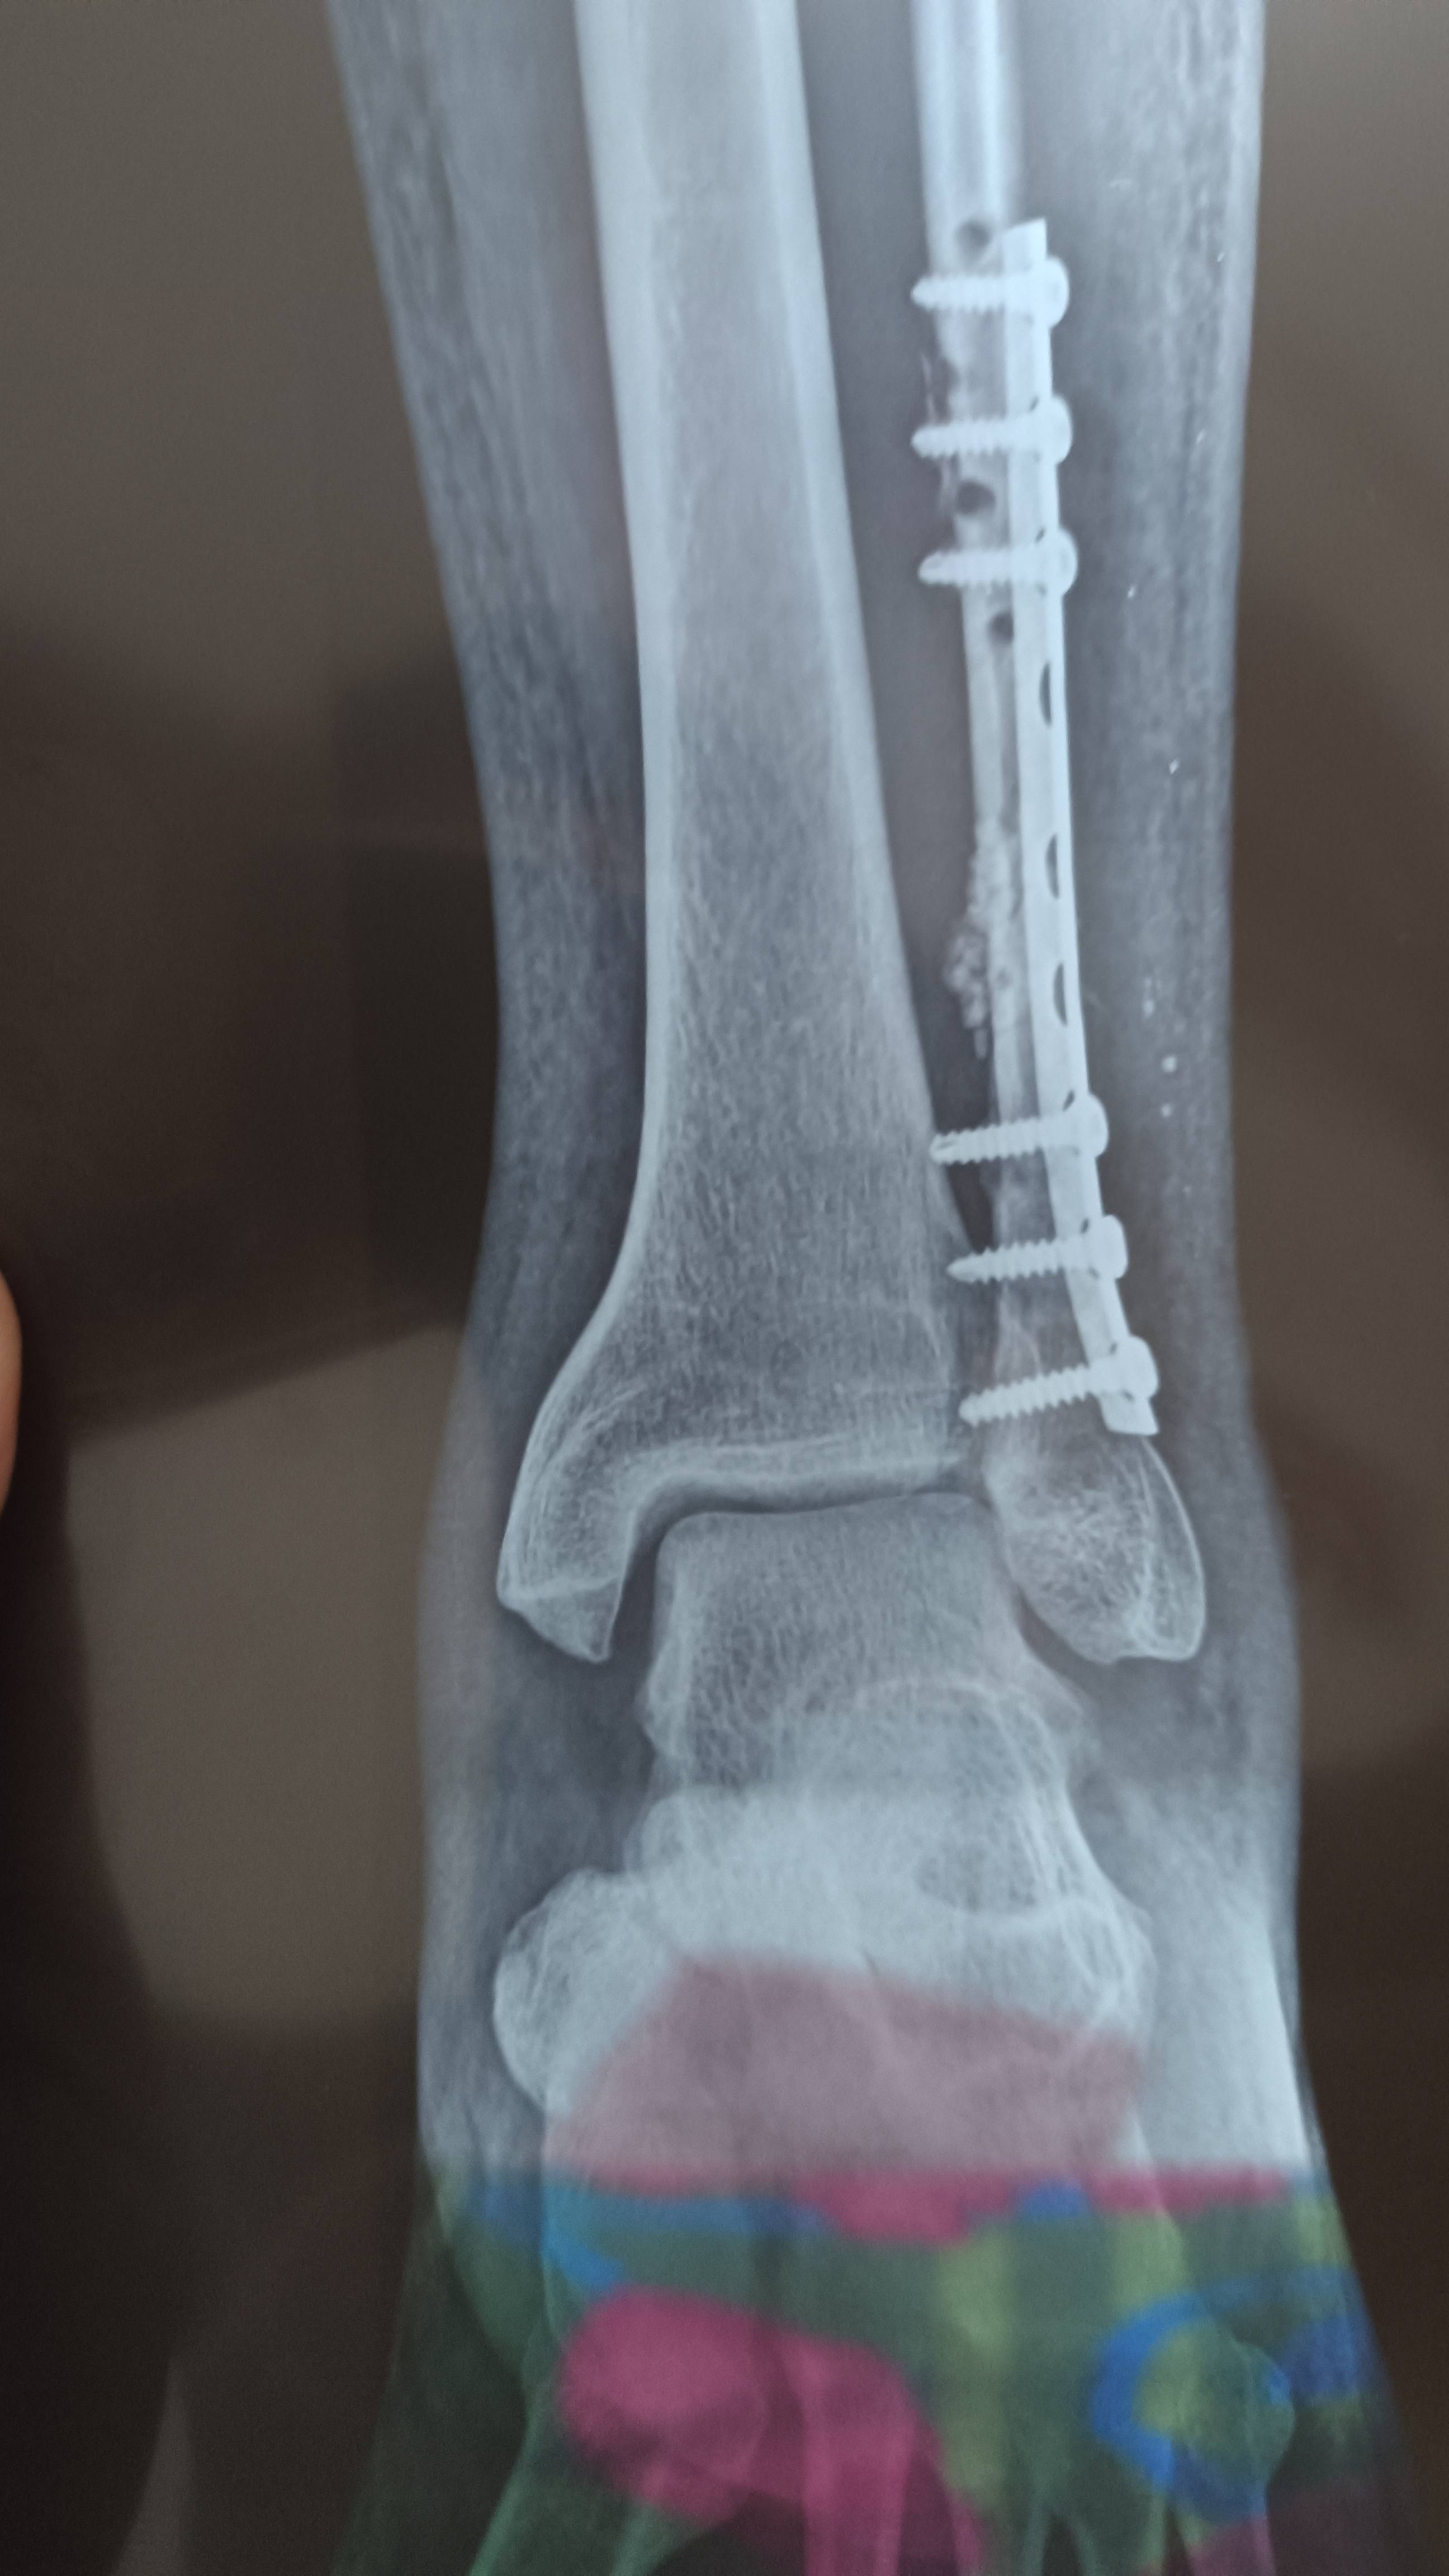

Namaste Dr sahab mera naam Arjun hai sir mera operation hua hai hai kya yeh sahi hai

Namaste Dr sahab kya ye xray sahi hai